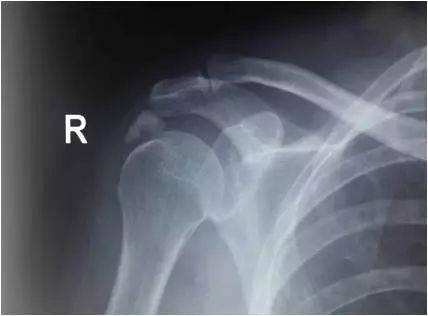

肩部骨质增生,钙化点

年龄较大或病程较长者,X线可见到肩部骨质疏松或局部钙化。